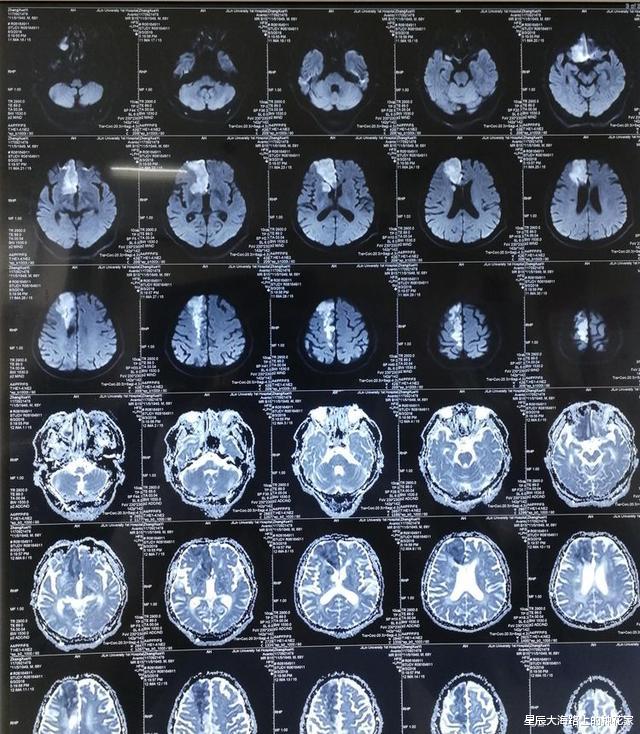

人去世的时候能意识到自己死了吗?去世后是否能知道自己已经死了这个状态的最大分歧在于:意识是否是独立的?从现代科学的角度来说 , 意识和大脑无数神经元通过复杂的网络连接产生的 , 两者之间是一个不可分割的整体 , 大脑通过神经元之间的各种生物电信号 , 构成人类大脑复杂的活动!

在这个过程中大脑需要消耗氧气和大量的能量 , 一般我们的大脑只占体重1%左右 , 但却消耗了20%的能量 , 大脑消耗大量能量就用来构筑意识了!所以当人体死亡时 , 脑部的供血就会消失 , 这就意味着供氧和能量同时消失 , 大脑的消耗量很大 , 几分钟之内就会发生不可逆的死亡!

此时发生的过程就像台式机的220V电源断电了 , 剩下就是大电容和电感中留存的能量 , 也许可以支撑几个正弦波周期 , 但关机是必然的!此时构筑意识的神经结构崩溃了 , 意识也就消失了!